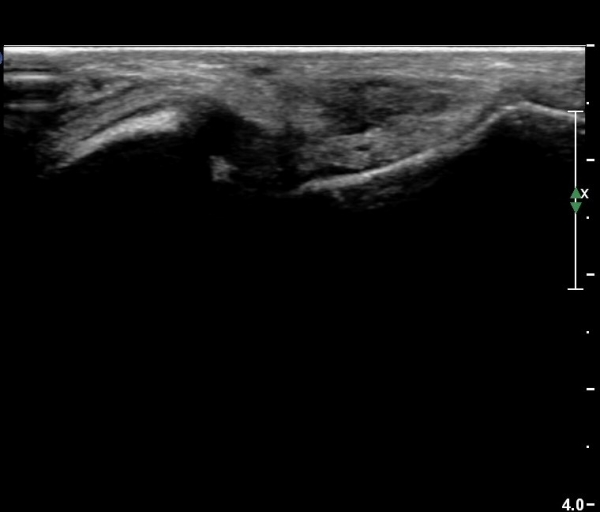

Àü°ÅºñÀδë Á¾´Ü¸é°Ë»ç¿¡¼­ ¾È´ë ºñ°ñ ºÎÂøºÎÀÇ Àú¿¡ÄÚ ºÎÁ¾°ú ºÎºÐÆÄ¿­ÀÌ °üÂûµÈ´Ù(»çÁø 4).

Àü°ÅºñÀδë Á¾´Ü¸é°Ë»ç¿¡¼­ Àü°ÅºñÀδëÀÇ Àú¿¡ÄÚ ºÎÁ¾ÀÌ °¨¼ÒÇϰí ÀδëÀÇ ¿¡ÄÚ°¡

Áõ°¡µÇ¾ú´Ù(»çÁø 3, 4).

Àü°ÅºñÀδë Á¾´Ü¸é°Ë»ç¿¡¼­  Àú¿¡ÄÚ ºÎÁ¾ÀÌ °¨¼ÒÇϰí ÀδëÀÇ ¿¡ÄÚ°¡ Áõ°¡µÇ¾ú´Ù(»çÁø 2, 3, 4).